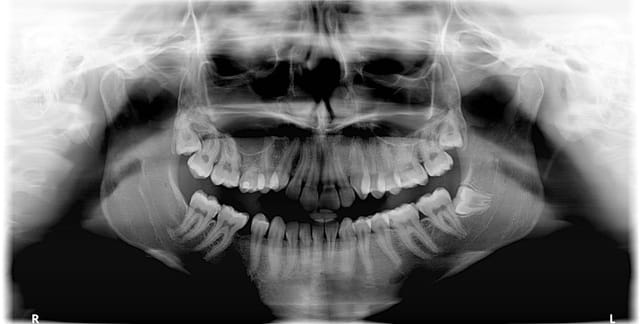

Patiente de 21 ans, 47 sensible à la pression mais pas au froid, avec cette image à l'apex.

A vos avis, qu'est-ce que c'est ?